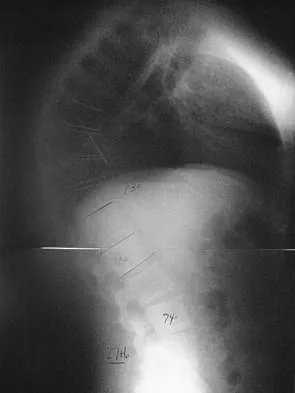

An otherwise healthy 70-year-old man has back and bilateral leg pain in an L5 distribution that is aggravated by standing more than 10 minutes or walking more than 100 feet. He has to sit to get relief. Neurologic and pulse examinations are normal. A radiograph and MRI scan are shown in Figures 4a and 4b. Treatment should consist of

The patient has a degenerative spondylolisthesis at L4-5 with associated spinal stenosis. His symptoms are consistent with neurogenic claudication. Based on these findings, the surgical treatment of choice is decompression and posterolateral fusion. Use of instrumentation is controversial. Laminectomy alone is reserved for the patient who is frail medically. There is no role for an anterior approach or for fusion alone without decompression. Fischgrund JS, Mackay M, Herkowitz HN, et al: Degenerative lumbar spondylolisthesis with spinal stenosis: A prospective, randomized study comparing decompressive laminectomy and arthrodesis with and without spinal instrumentation. Spine 1997;22:2807-2812.